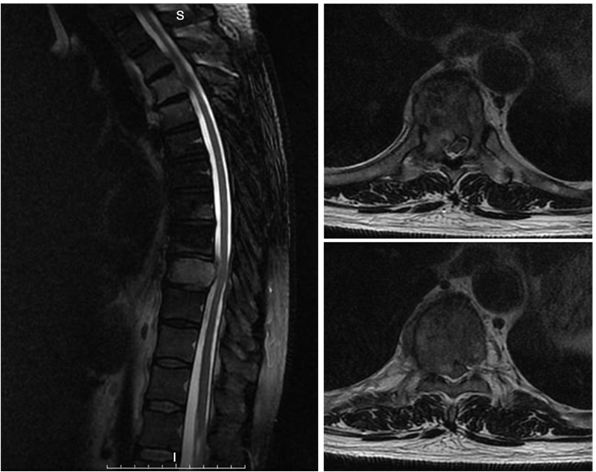

2025-6-12 胸椎磁共振MR(图2):T9椎体右份及右侧椎弓根骨质破坏,椎体周围软组织增厚突入椎管,压迫硬膜囊及右侧神经根。

图2 :胸椎磁共振